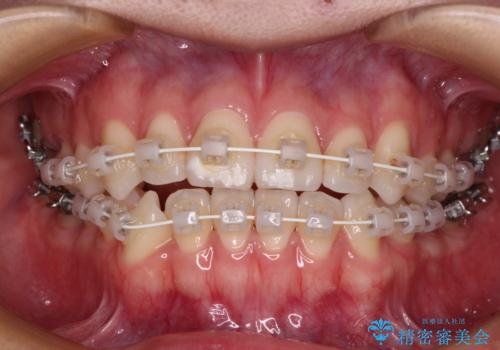

- 矯正装置

- 審美装置

装置はワイヤー装置でもインビザラインのマウスピースでもどちらでも適用でしたが、自己管理の煩わしさを嫌い、ワイヤー矯正にて治療を行うこととしました。

ワイヤー矯正を選択されたため、鋏状咬合を確実に改善するために補助装置を併用することとしました。

ワイヤー装置でもマウスピースでも、どちらでも適用の症例でしたが、片側の鋏状咬合はマウスピース矯正ではしっかりと改善できる可能性が低いことや、何と言っても自己管理の煩わしさがないことから、ワイヤー装置を選択されました。